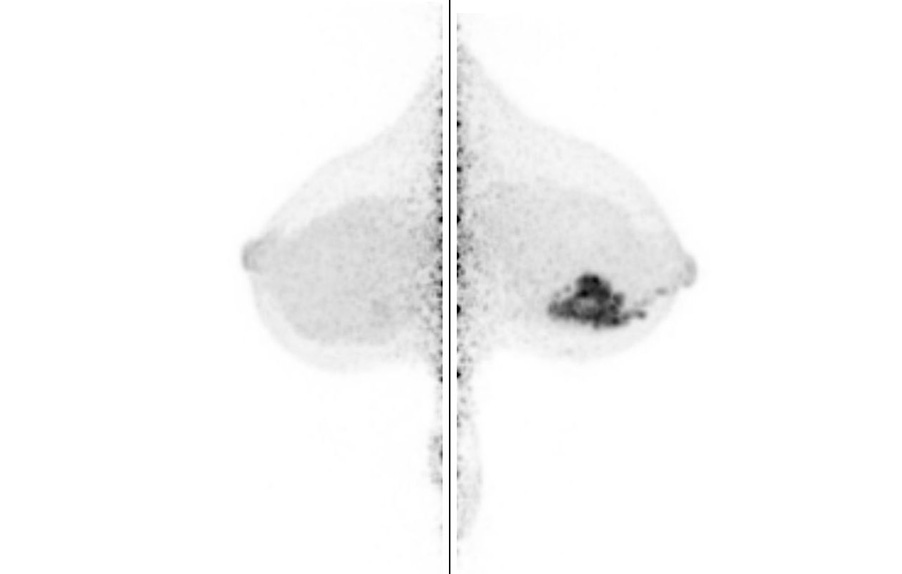

Breast / Case1 : FDG

CC-MIP

Courtesy : Kindai University Hospital

- Imaging protocol

- Injected dose: 2.64 MBq/kg, 18F-FDG

- Scan time: 5 minutes